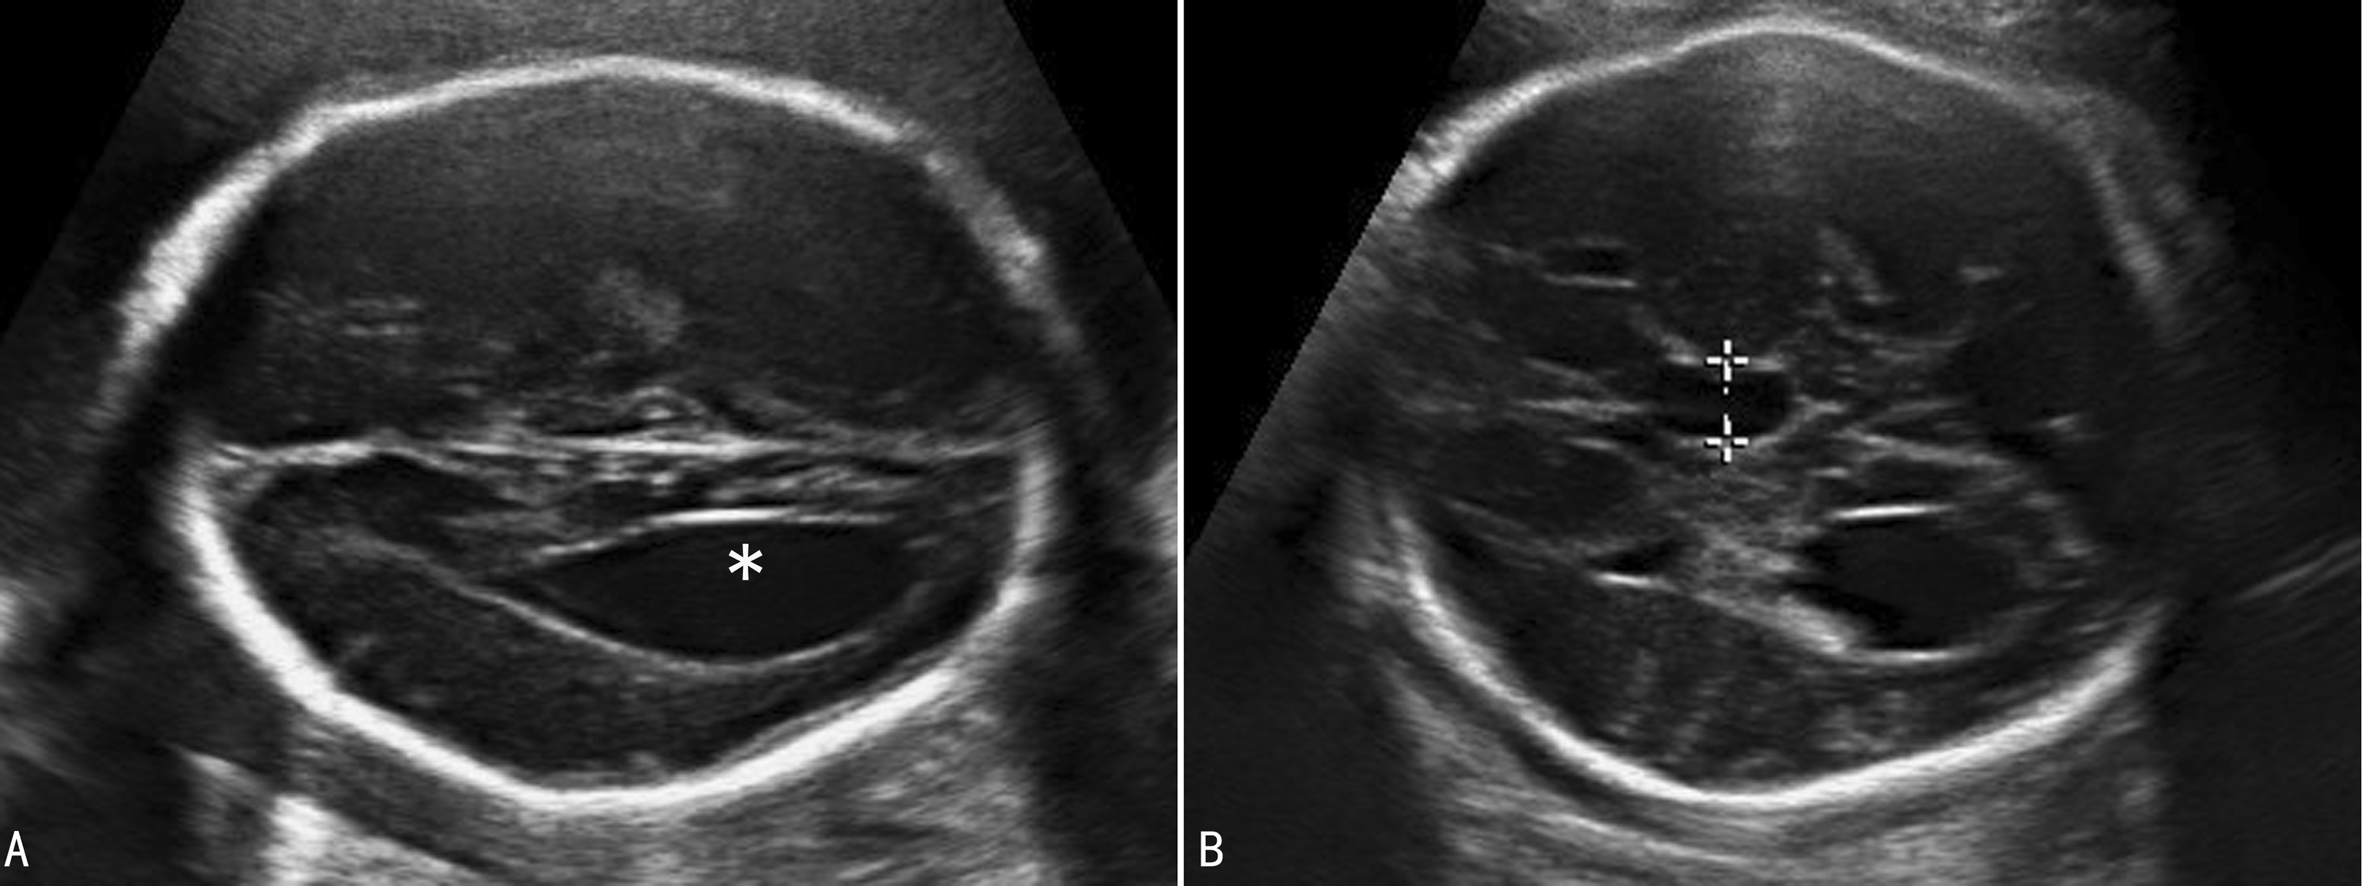

1. 侧脑室前角及侧脑室体部偏离中线,向外侧展开,侧脑室前角变窄呈尖角峰状,形成“公牛角征”(图3A)。双侧脑室呈平行状,侧脑室后角扩张,与变窄的前角一起呈现“泪滴状”(图3B)。

图3胼胝体缺失脑室变化

2. 透明隔腔消失(图4)。

图4胼胝体缺失透明隔强消失